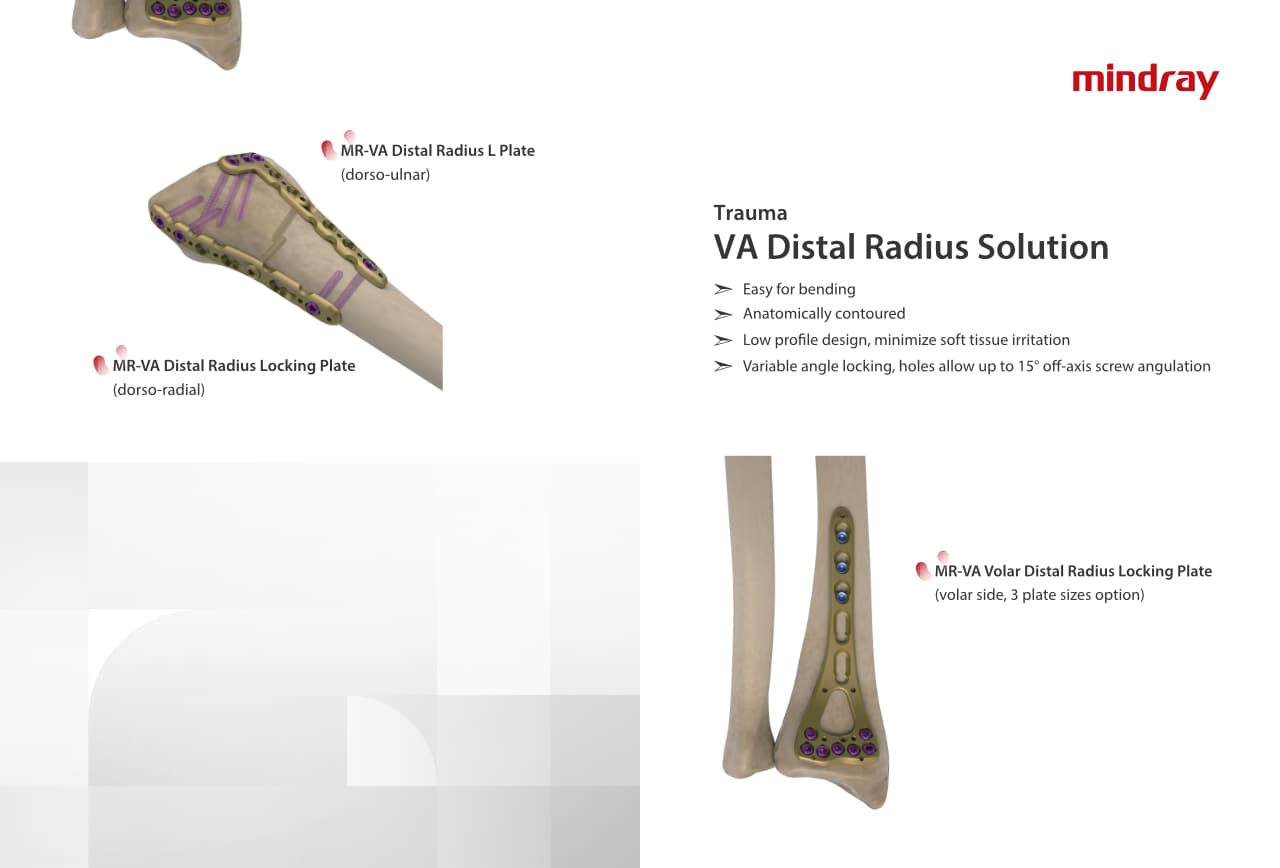

РһСҖСӮРҫРҝРөРҙРёСҮРөСҒРәРҫРө РҝРҫРҙСҖазРҙРөР»РөРҪРёРө РәРҫРјРҝР°РҪРёРё Mindray, СҖР°СҒРҝРҫР»РҫР¶РөРҪРҪРҫРө РІ РЈС…Р°РҪРө, СҸРІР»СҸРөСӮСҒСҸ РҫРҙРҪРёРј РёР· РІРөРҙСғСүРёС… РҝСҖРҫРёР·РІРҫРҙРёСӮРөР»РөР№ РҫСҖСӮРҫРҝРөРҙРёСҮРөСҒРәРҫР№ РҝСҖРҫРҙСғРәСҶРёРё РёР· РҡРёСӮР°СҸ. РһРҪРҫ Р·Р°РҪРёРјР°РөСӮСҒСҸ РёСҒСҒР»РөРҙРҫРІР°РҪРёСҸРјРё Рё СҖазСҖР°РұРҫСӮРәРҫР№, РҝСҖРҫРёР·РІРҫРҙСҒСӮРІРҫРј Рё РјР°СҖРәРөСӮРёРҪРіРҫРј СӮСҖавмаСӮРҫР»РҫРіРёСҮРөСҒРәРёС… Рё СҒРҝРёРҪалСҢРҪСӢС… РёР·РҙРөлий, РҝСҖРҫРҙСғРәСҶРёРё РҙР»СҸ Р°СҖСӮСҖРҫРҝлаСҒСӮРёРәРё Рё РҙСҖСғРіРёС… С…РёСҖСғСҖРіРёСҮРөСҒРәРёС… РёР·РҙРөлий. РЎ РјРҫРјРөРҪСӮР° СҒРІРҫРөРіРҫ РҫСҒРҪРҫРІР°РҪРёСҸ РІ 1999 РіРҫРҙСғ РјСӢ СғСҒРҝРөСҲРҪРҫ РҝСҖРҫСҲли СҒРөСҖСӮифиРәР°СҶРёСҺ ISO 9001, ISO 13485 Рё CE, РІСӢРҙР°РҪРҪСғСҺ T?V Рё СҚРәСҒРҝРҫСҖСӮРёСҖСғРөРј РҝСҖРҫРҙСғРәСҶРёСҺ РІ РұРҫР»РөРө СҮРөРј 50 СҒСӮСҖР°РҪ РҝРҫ РІСҒРөРјСғ РјРёСҖСғ.